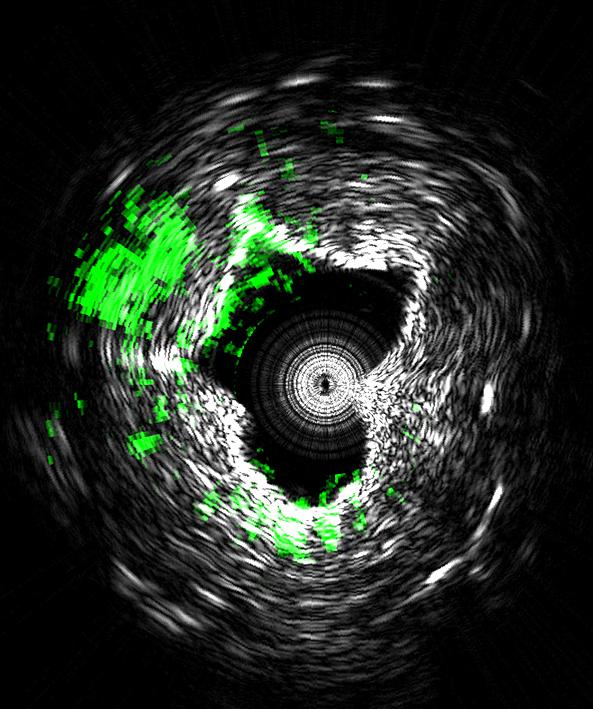

IMAGE CAPTION:

This image is taken using a new type of medical imaging technology that could diagnose cardiovascular disease by measuring ultrasound signals from molecules exposed to a fast-pulsing laser. The system, called intravascular photoacoustic imaging, takes precise three-dimensional images of plaques lining arteries and identifies deposits that are likely to rupture and cause heart attacks. This cross-sectional view of an artery shows lipids (green) deposited inside the arterial wall Black and white indicate contrast showing the cross-sectional geometry. (Purdue University Weldon School of Biomedical Engineering image/Ji-Xin Cheng)

The system takes precise three-dimensional images of plaques lining arteries and identifies deposits that are likely to rupture and cause heart attacks, said Ji-Xin Cheng (pronounced Jee-Shin), a professor in Purdue University's Weldon School of Biomedical Engineering and Department of Chemistry.

The imaging reveals the presence of carbon-hydrogen bonds making up lipid molecules in arterial plaques that cause heart disease. Research findings are detailed in a paper appearing online today (Nov. 4) in the Nature journal Scientific Reports .